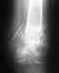

Действительно, тут лучше пластину убрать.

При ревизионной операции поглядеть, возможно, получится попытка реконструкции из того, что осталось. Эндопротезирование, пожалуй, наиболее практичный вариант.